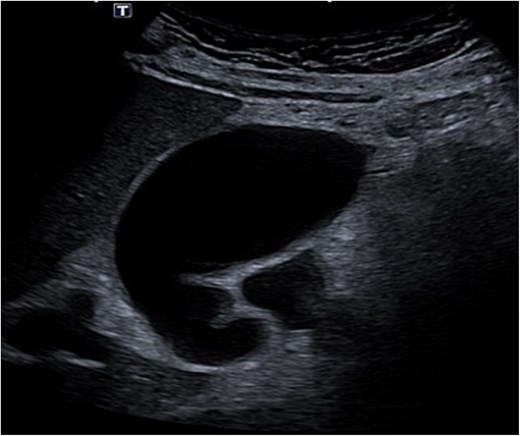

Despite the absence of abdominal symptoms, a computed tomography of the abdomen and pelvis (CTAP) was performed due to markedly elevated lipase levels. The CTAP (Figs 3–5) revealed evidence of acute pancreatitis (Fig. 5, arrow), with a complex peripancreatic fluid collection (Fig. 3, arrow). Additionally, a focal thrombus was observed within the portal venous confluence (Fig. 4, arrow). Further ultrasound of the gallbladder was negative for gallstones (Fig. 6), ruling out gallstone-induced pancreatitis.